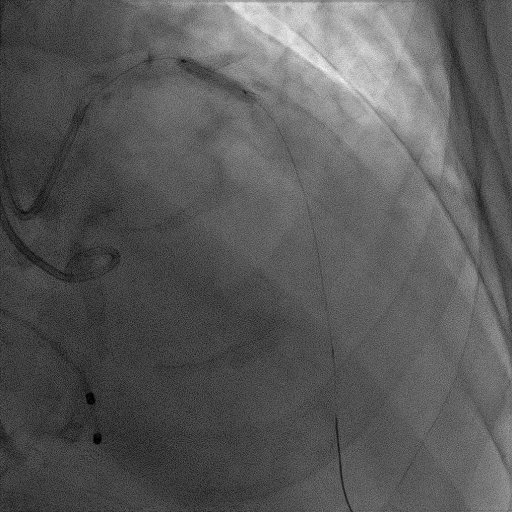

造影提示微少量返流,压力监测提示主动脉瓣压差7mmHg

患者麻醉方式为全麻,建立静脉通路后,穿刺右侧股静脉,预埋ProGlide缝合器,食道超声指导下房间隔穿刺成功,将Superstiff导丝送至左房,应用18F鞘管扩张穿刺部位,沿导丝将导引导管送入左房,MitraClip调整后顺利到达二尖瓣目标位置,在X线及食道超声辅助下,将Mitraclip NTR成形夹精确定位后,成功夹合二尖瓣A2-P2区,超声显示反流明显减少,多切面证实夹合组织充分,肺静脉多普勒波形由反向恢复正常,手术顺利结束,安返普通病房。